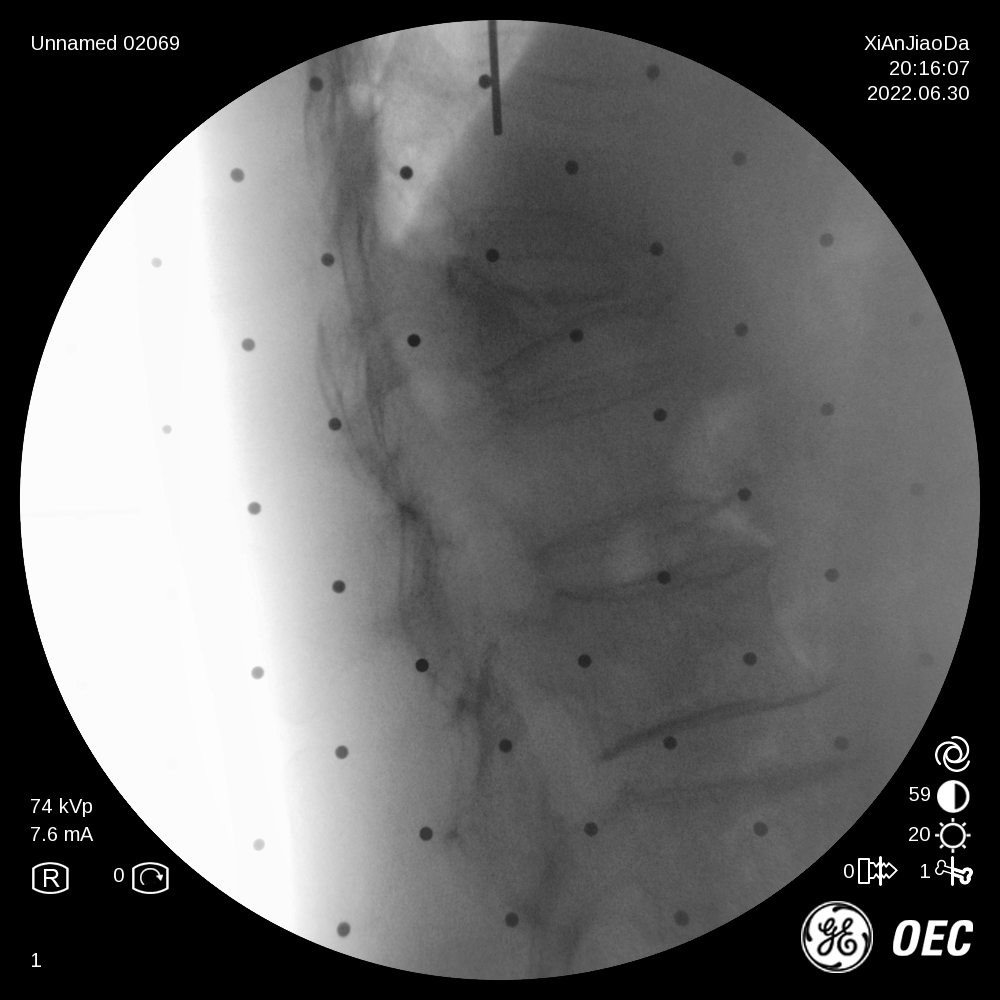

患者为一69岁女性,6月前摔倒后出现腰部疼痛伴活动受限,保守治疗后效果不佳遂来我院,经过诊断分析,该患者椎体重度压缩性骨折,重度骨质疏松致透视下骨性标志不明显,且存在轻微脊柱侧弯。王坤正主任团队最终决定运用智能化的手段,在局麻下行机器人辅助经皮椎体球囊扩张成形术,采取直观定位技术,相较其他机器人的定位导航技术,无需定位标志物,使得手术能够在全程局麻下操作,保证医生能得到患者的实时反馈,可使手术更精准、更便捷、更安全。

术前,王坤正主任团队采集患者的三维CT数据并将其导入到机器人术前规划系统中,机器人工程师与其配合确定穿刺位置、角度、深度等信息,制定出适合患者本人的个性化手术方案并在术中由机器人予以实施。

在该机器人辅助手术过程中,仅需通过正侧位进行伤椎识别,通过软件将正侧位透视图与术前规划数据的结合,即可得到病人伤椎的姿态以及实际的穿刺角度,之后机械臂根据软件参数进行精准定位,手术医生在机械臂引导下一次性进针成功,并对进针位置角度表示满意,整个过程少于20分钟,实现了手术的更精准化、高效化。相较于传统定位流程,术前规划只能保存在医生脑海中,术前与术中流程无法很好的衔接,术中穿刺依赖医生丰富的经验,对于情况复杂的病人,术中需要反复试验,导致手术时间延长、患者受辐射量增加。后续放置球囊、注入骨水泥等操作则同传统手工操作。